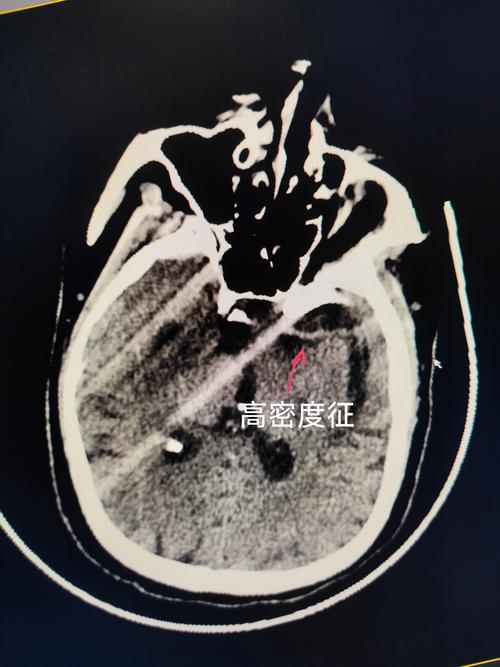

C. 左侧移位 (Shifted to the Left)

- 通俗理解:原本在正中央的“中线结构”,现在被推向了左边。

- 深层含义:这说明右侧大脑的压力,比左侧大脑的压力要大得多,就像一个气球,如果一边被用力挤压,中间的隔膜就会被推向另一侧。

- 中线被挤压:右侧巨大的压力,像推土机一样,把位于正中央的“中线结构”(大脑镰等)硬生生地推向了压力较小的左侧。